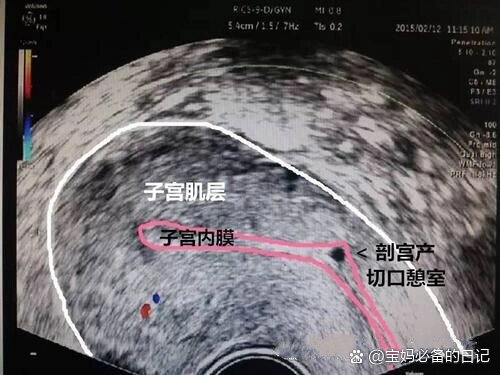

子宫瘢痕憩室是什么病

剖宫产瘢痕憩室是剖宫产术后子宫切口处因愈合缺陷等,在子宫瘢痕部位形成的与宫腔相通的凹陷或腔隙形成原因手术相关因素中,剖宫产手术方式缝合技术影响较大如子宫下段横切口位置不当缝合过密或过疏,都不利于切口愈合,增加憩室形成...